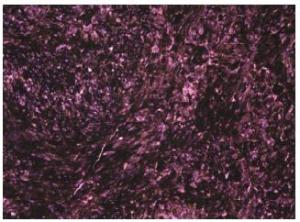

20170308102059 Figure 3 Hematoxylin and Eosin (H&E) staining, ×400. Variable amounts of melanin with areas of necrosis and foci of parenchymal infiltration and nuclear pleomorphism with occasional mitotic figures are observed.